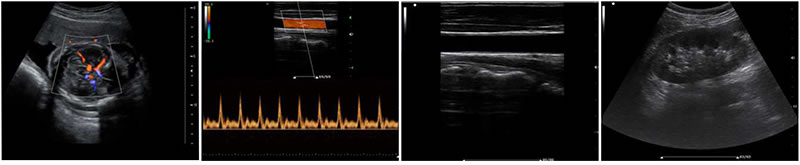

B、C、PW、CW、BCD三功、大角度偏转成像、实时宽景成像、梯形成像(仅支持线阵)、解剖M型、彩色M型成像、组织多普勒成像、3D/4D成像

成像模式

·B-模式 ·M-模式 ·THI-模式 ·Color 模式(CFM)

·PDI 模式 ·PW 模式 ·CW 模式

显示模式

·B、D a·B、4B ·B+Color、D a·B+Color、4B+color

·B+ PDI、D a·B+ PDI、4B+PDI ·M、B+M

·B+PW ·B+color+PW

·B+DPI+PW ·B+CW

·B+color+CW ·B+PDI+CW

·B+AM ·梯形成像 ·复合成像